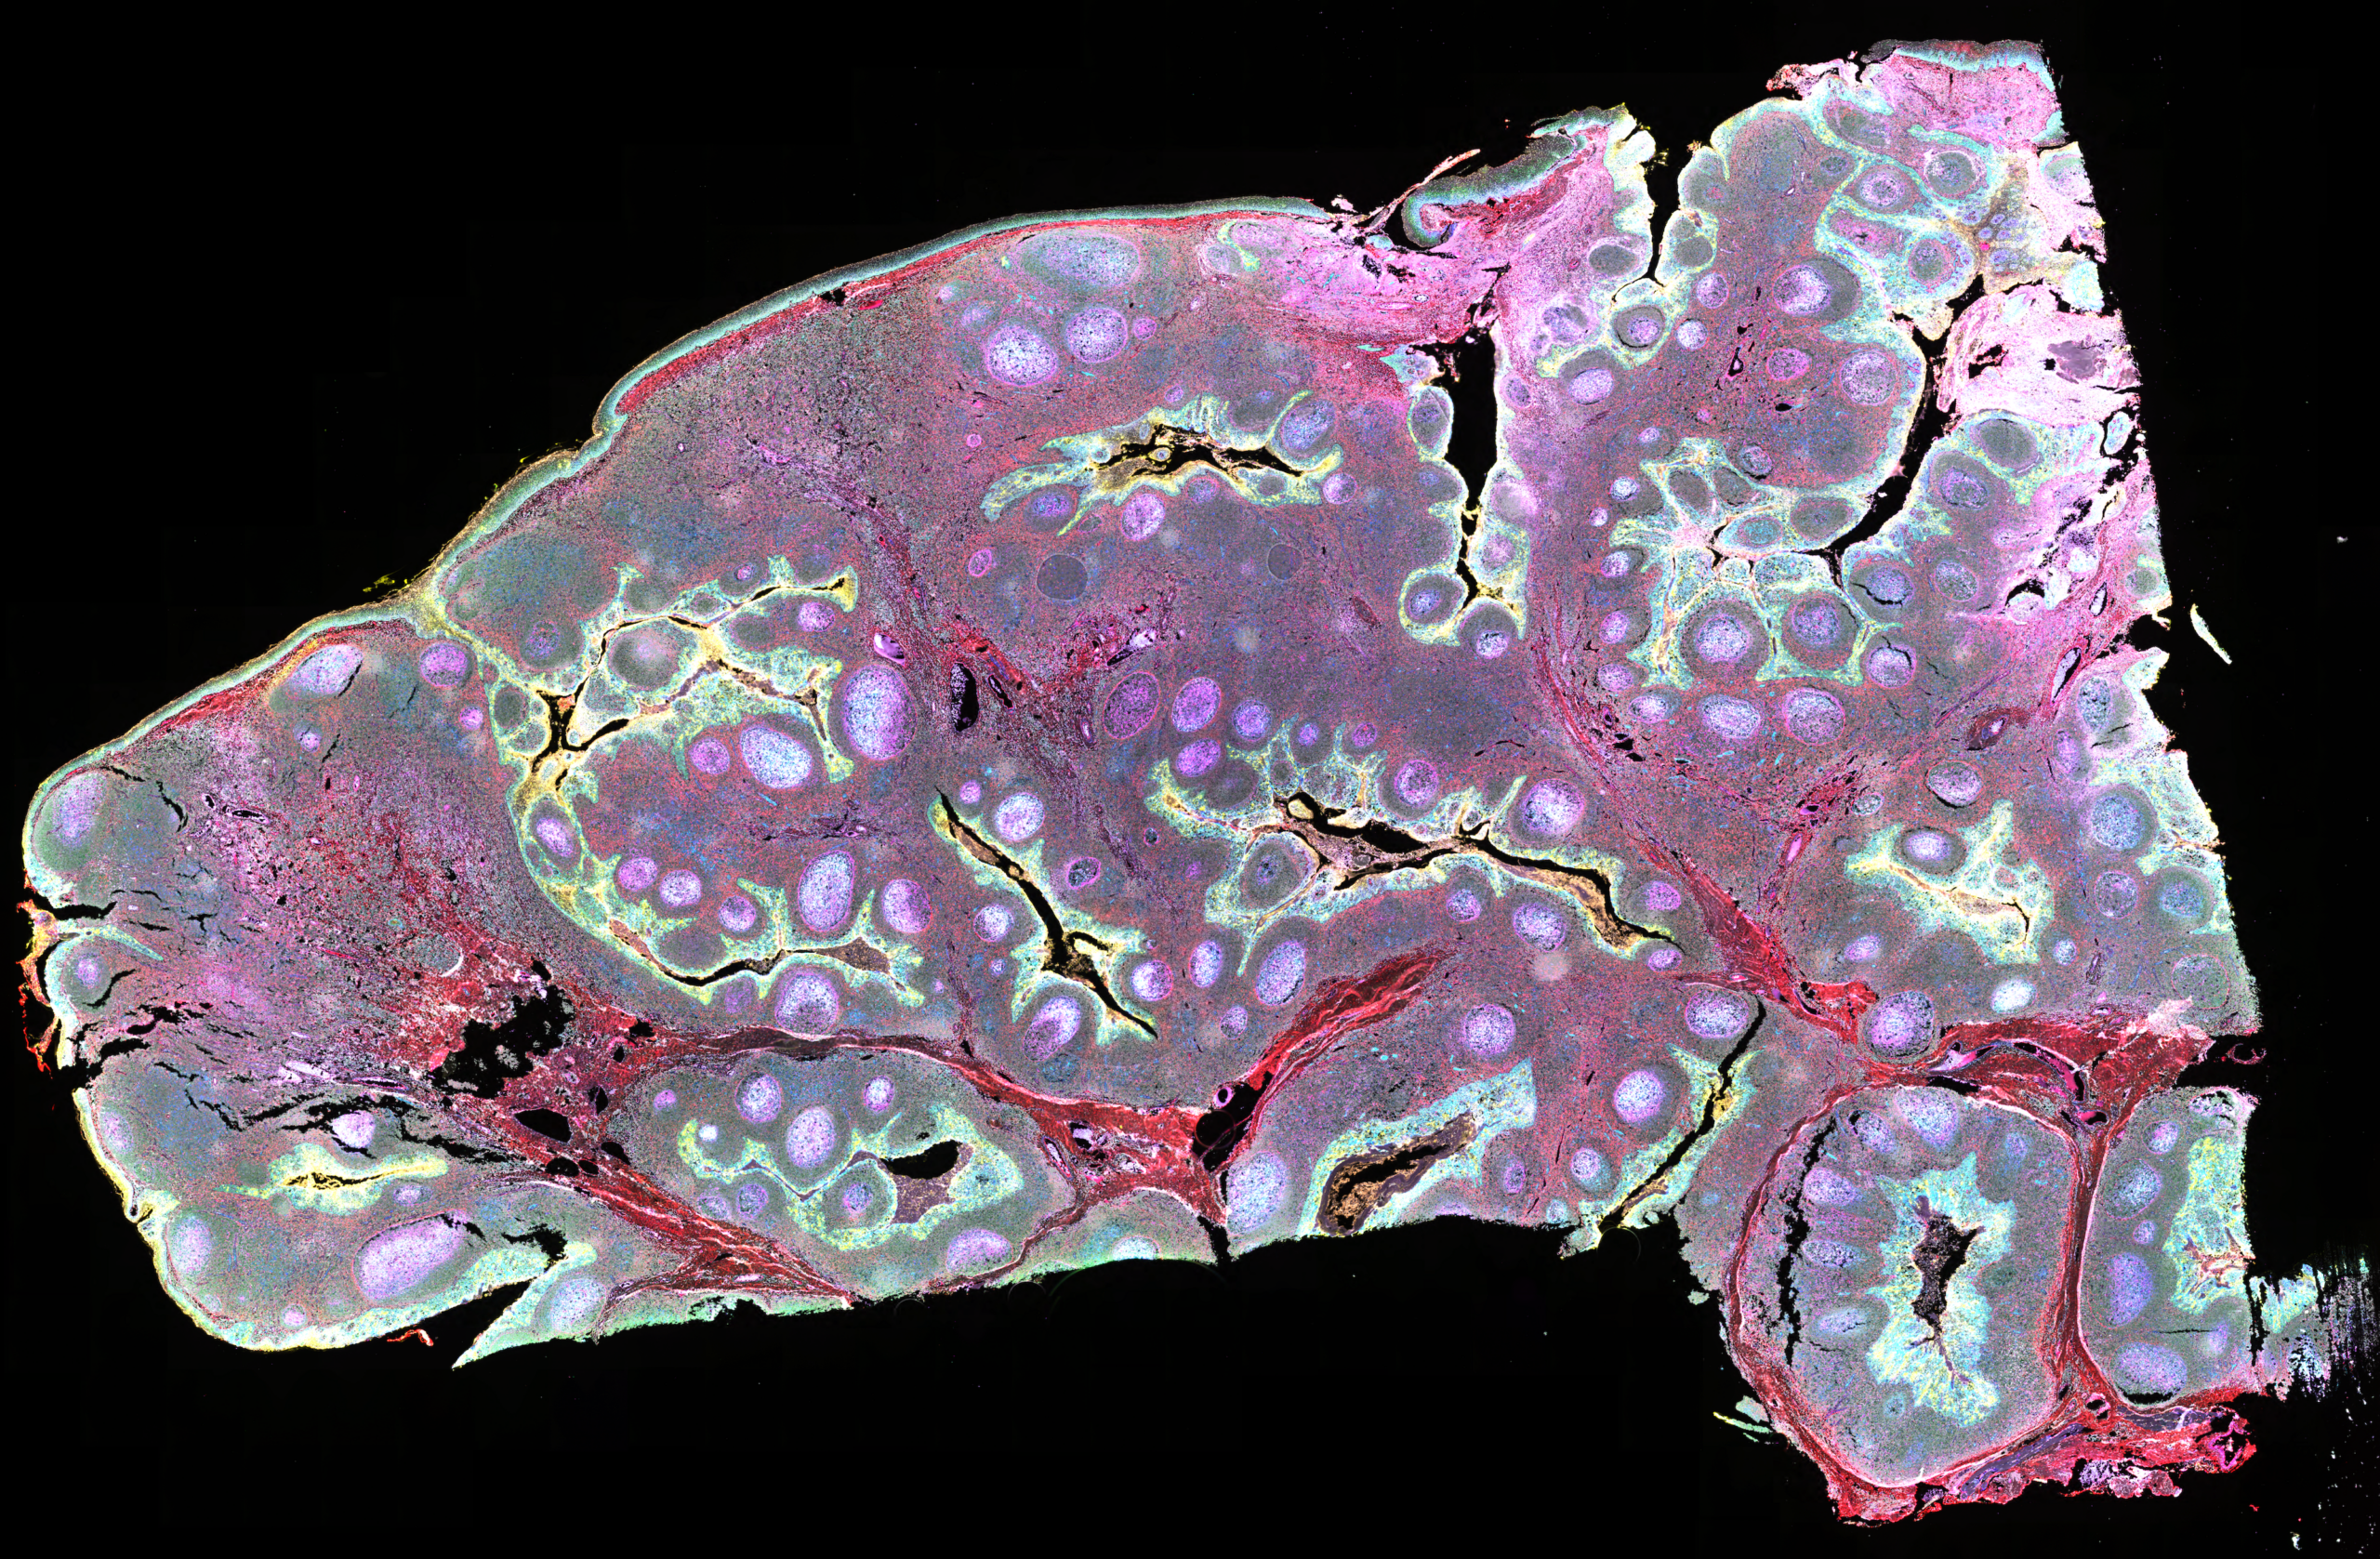

Omni is a multiplex in situ proximity ligation assay with a fluorescent readout, enabling the simultaneous detection of up to 9 protein–protein interactions, post-translational modifications, or single protein targets with high specificity and sensitivity. The technology is validated for use in human FFPE tissue samples*.

Omni is built on Navinci’s proprietary in situ proximity ligation technology, using target-specific primary Navenibodies conjugated to proprietary oligonucleotide arms. Each target is recognized by a unique pair of Navenibodies – either binding two different proteins to detect interactions, or two distinct epitopes on the same protein for highly specific single-target detection. When bound in close proximity, the oligonucleotides generate a strong, amplified fluorescent signal. Distinct fluorophores enable simultaneous detection of multiple targets within the same sample.

With Omni, this proven technology is expanded to enable multiplex detection of up to 9 targets in a single experiment. Learn more about the Omni technology and workflow.